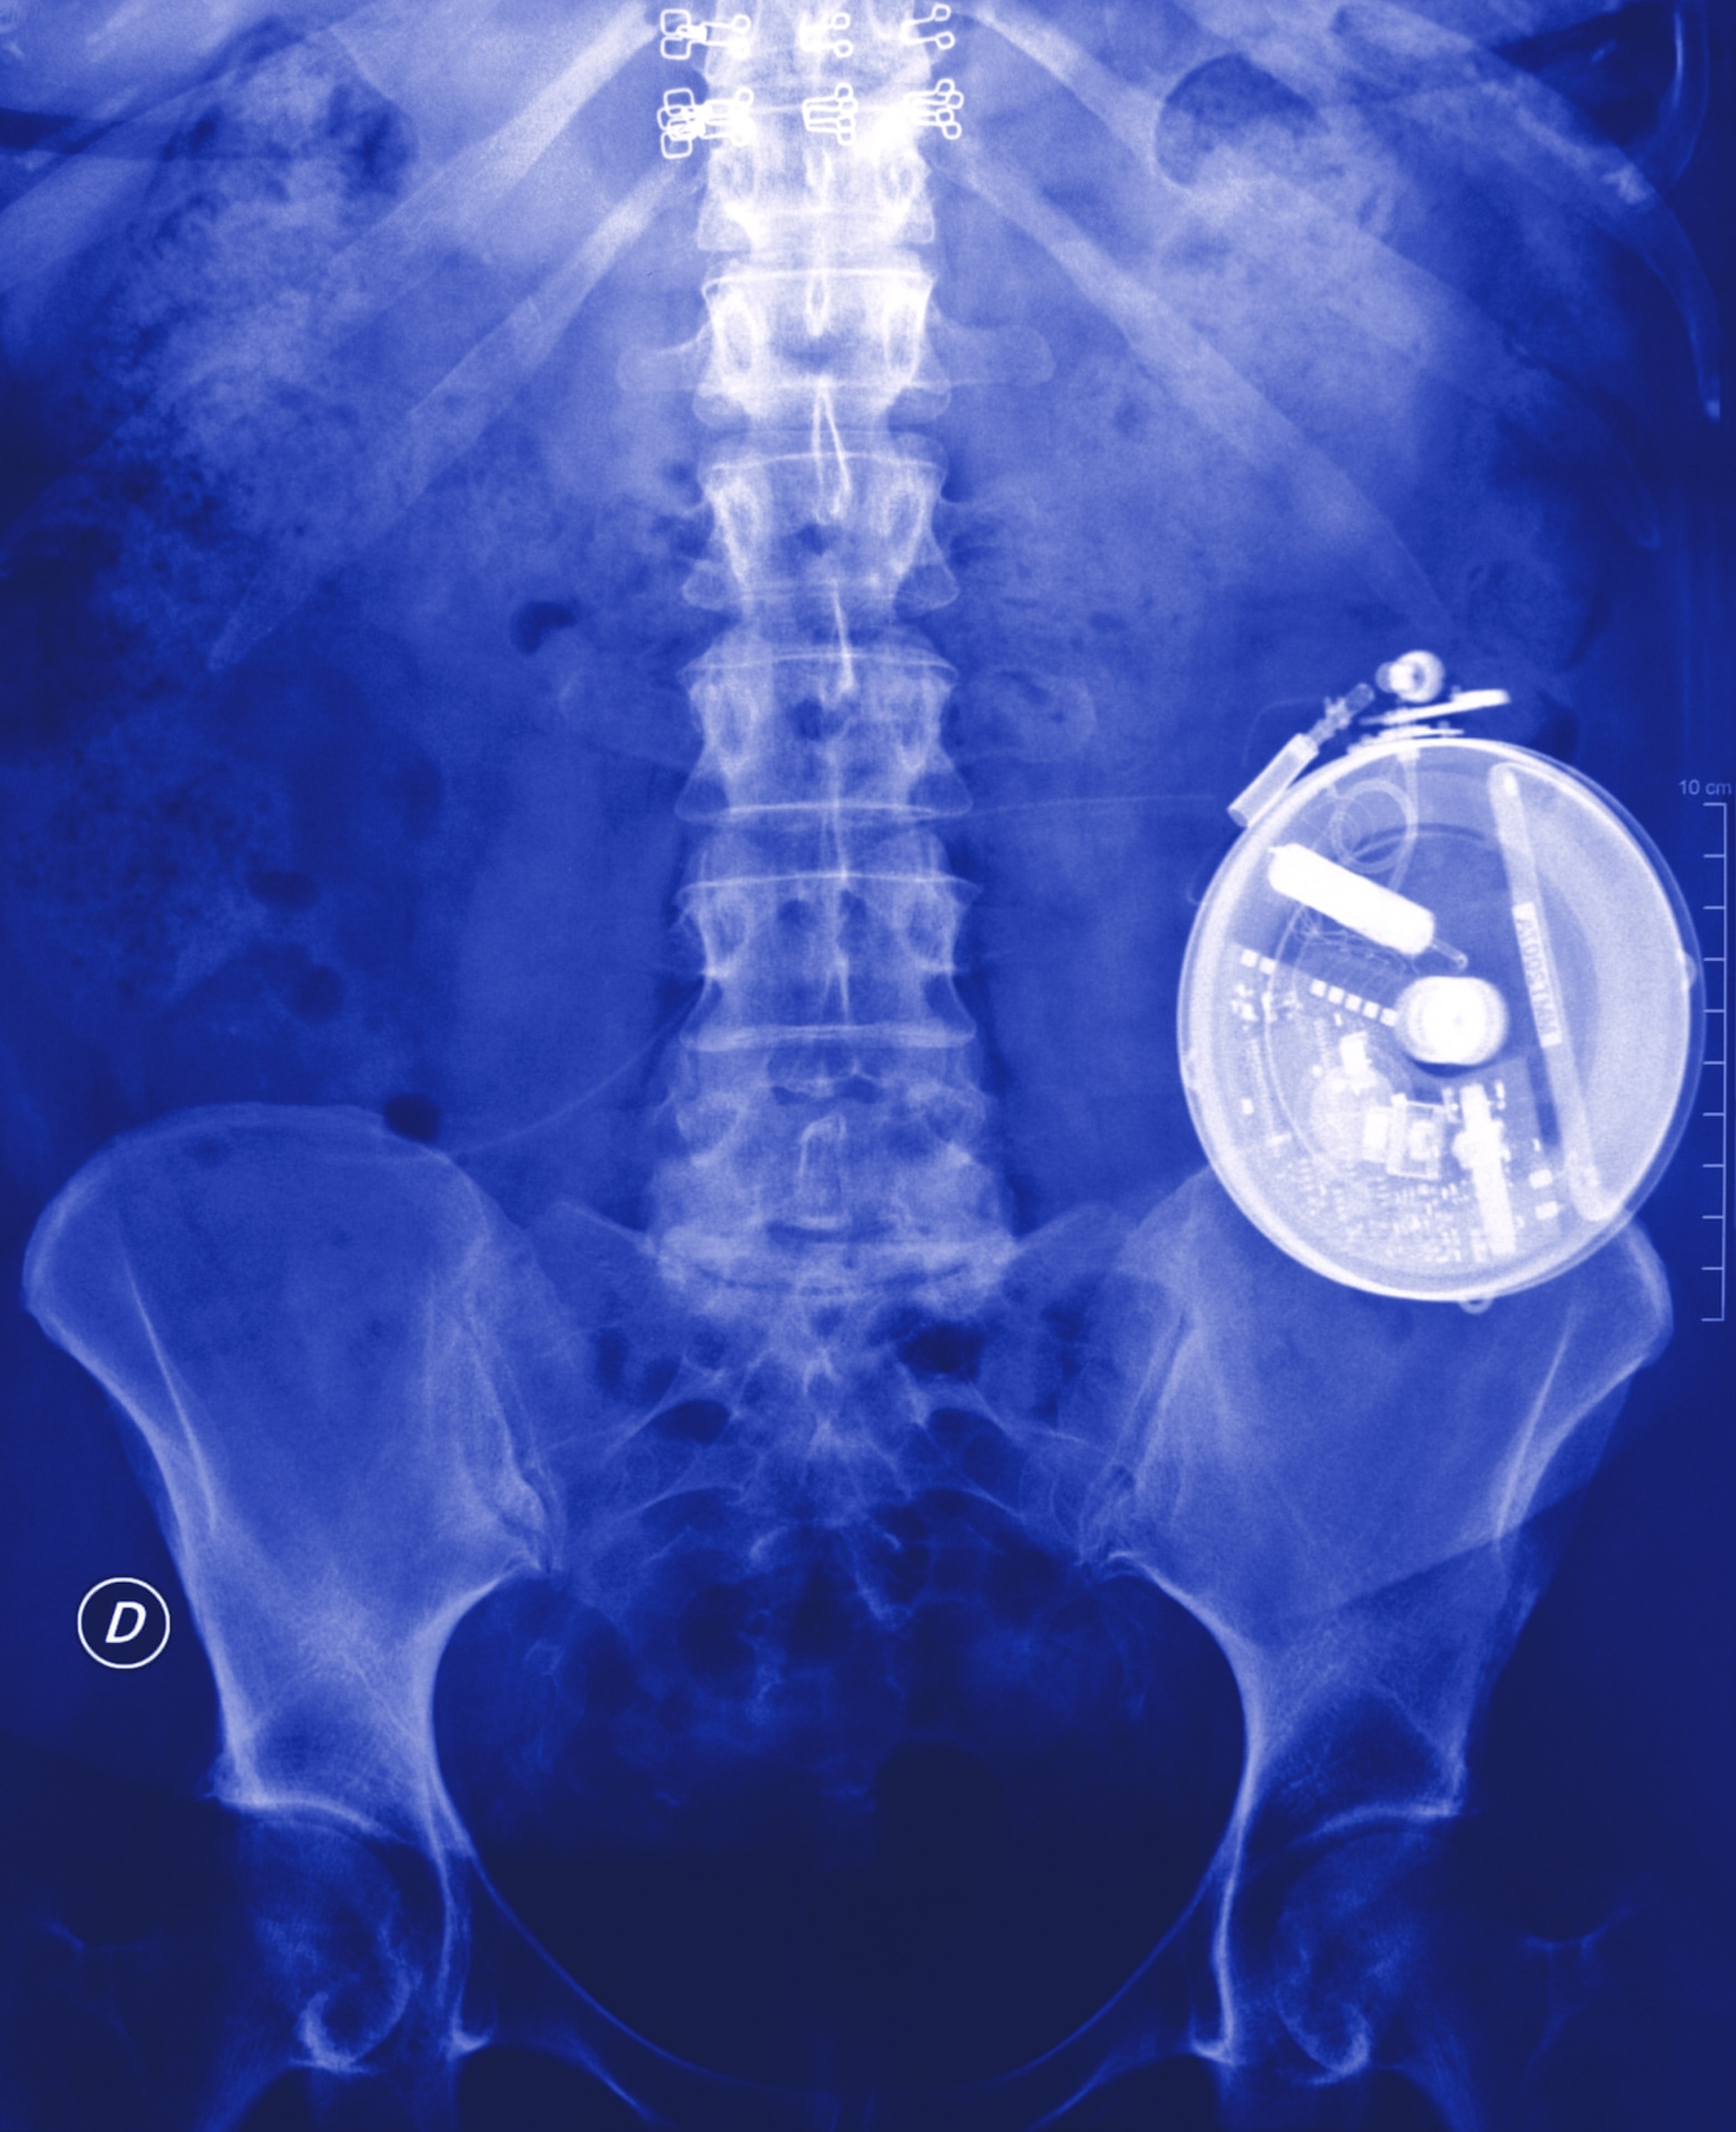

While Shapiro’s protocol became available for patients who could not control their diabetes by other means, it was never broadly prescribed. The cadaveric islet cells required immunosuppressant drugs, which risk new infections and novel cancers. The islet cells also originate from a finite resource: deceased people. Patients typically need cells from two to three donors, and it’s not a one-time thing. The cells sometimes die, necessitating top-ups. Pokerznik, for instance, was off supplemental insulin within weeks of her first transplant in 1999. Then in 2003, she was back on insulin. In 2014: off again. In 2018: on. Since 2019, she has been off insulin.

Pokerznik was Shapiro’s second patient in the trial. “It was hard for me to even wrap my mind around,” she says, “because I’d been diabetic for so long.” Later, Shapiro also performed the procedure on McLeod and Coleman. The women say the therapy liberated them from the minute-by-minute calculations they had to make when managing their disease using pharmaceutical insulin. It also saved them from the constant crashes. “It changed a lot,” Coleman says. “Really, for me,” McLeod says, “there was no other option.”